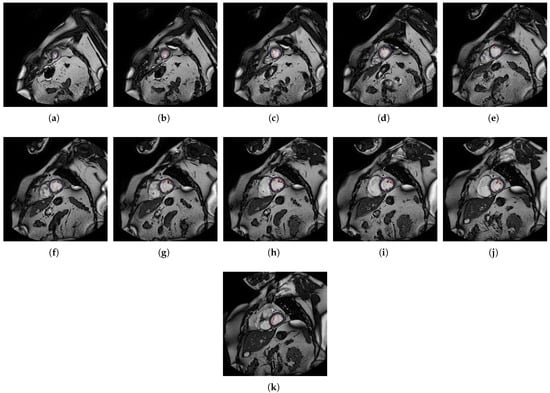

- The different MSERs are detected in a centered ROI of each input image by the use of OpenCV [23]. As the LV cavity is normally represented by a circular shape, the centroid of each MSER detected is computed in order to automatically identify the left ventricle cavity anywhere in the image and for applying the convex hull.

- The previous application of the convex hull allows a second refining to optimize the search process of the external layer and the trabeculae areas. The parameter e-expand is redefined and adjusted to accurately determine the external layer of the compact zone, thanks to plotting several lines from the centroid of the LV to reach the points of the external layer. This parameter establishes the distance of the lines between the centroid of the LV cavity and the possible space where the external layer can be found, taking into account the particular features of genetic cardiomyopathies. We optimized the parameter e-expand for different situations or possible cardiomyopathies.